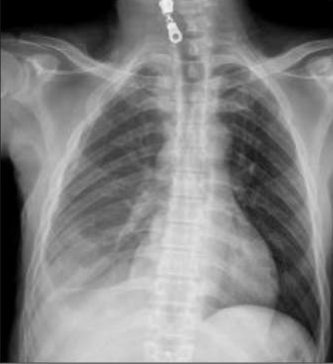

| X-ray Image | Baseline | M2TR | R2Gen | Ours |

![]() |

Pneumothorax gauche de moyenne abondance./Silhouette cardiaque dâaspect normal./Absence dâanomalie mĂ©diastinale./Absence dâĂ©panchement pleural./Absence dâanomalie du gril costal./ | Pneumothorax gauche de grande abondance./Contours cardiaques rĂ©guliers./MĂ©diastin sans anomalies dĂ©celables./ Aucun Ă©panchement pleural dĂ©tectĂ©./Structure du gril costal normale. | Pneumothorax de petite abondance./Aucune anomalie visible au niveau du mĂ©diastin./Pas de prĂ©sence d'Ă©panchement pleural./ | Pneumothorax bilatĂ©ral de moyenne abondance./Configuration normale de la silhouette cardiaque./MĂ©diastin clair, sans irrĂ©gularitĂ©s./Absence d'Ă©panchement pleural./Aucune lĂ©sion du gril costal observĂ©e./ |